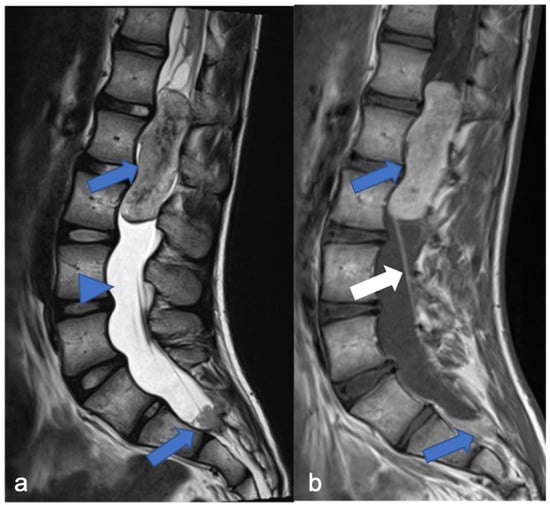

2.2. Diffuse Leptomeningeal Glioneuronal Tumor